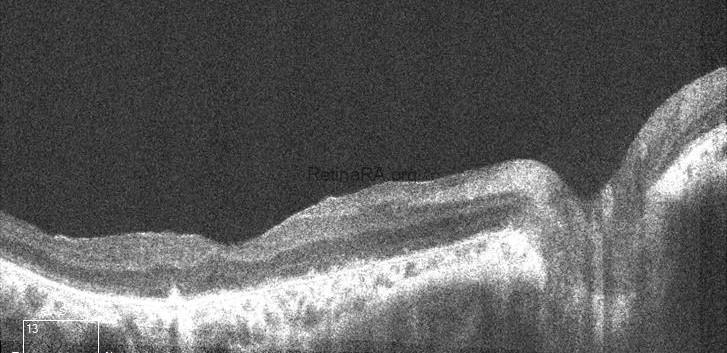

The scan of the right eye shows marked thinning of the outer retinal layers, particularly involving the outer nuclear layer and ellipsoid zone. The foveal contour is preserved; however, there is significant disruption and attenuation of the IS/OS junction and RPE band, consistent with advanced rod-cone dystrophy. In the left eye, generalized outer retinal atrophy is seen with loss of the photoreceptor integrity line and irregularity in the RPE layer. The foveal depression is shallow, and parafoveal architecture is disorganized, indicating chronic degenerative changes.

Multimodal imaging in Bardet-Biedl syndrome reveals characteristic features of retinal degeneration. Fundus photography typically shows attenuated vessels, waxy optic disc pallor, and bone spicule pigmentation in the mid-periphery. Fundus autofluorescence often demonstrates patchy areas of hypoautofluorescence correlating with RPE loss. OCT reveals outer retinal thinning, disruption of the ellipsoid zone, and foveal architecture loss in later stages. Electroretinography shows diminished or extinguished scotopic and photopic responses, confirming widespread rod-cone dysfunction.